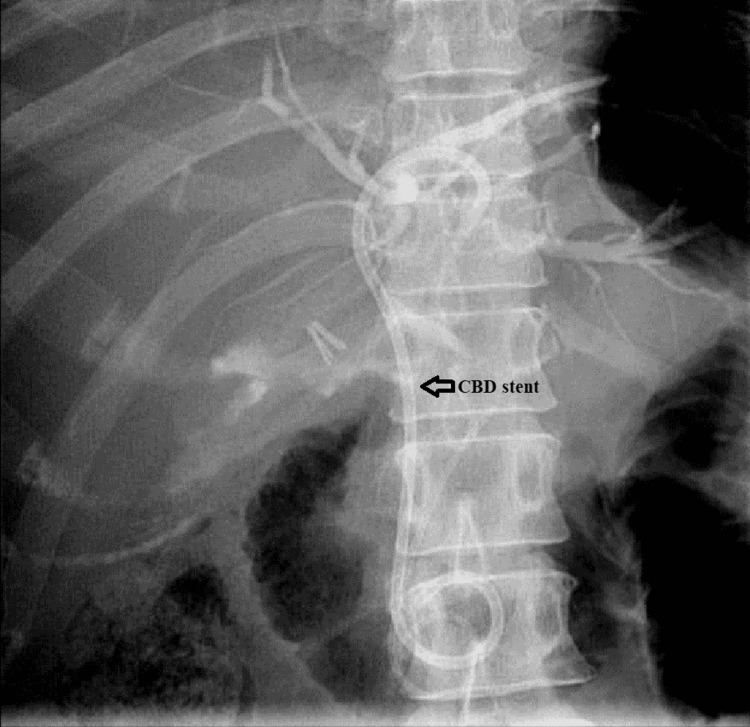

The patient was maintained on supportive treatment and close observation and was planned for endoscopic retrograde cholangiopancreatography (ERCP) and stenting. It showed a filling defect at the most distal part of CBD. Deep cannulation of CBD was achieved. A contrast leak was detected from the cystic stump with normal intra- and extrahepatic bile ducts. A partial sphincterotomy was performed, and a double pigtail stent was placed at the left hepatic duct, which eventually showed good contrast and bile drainage into the duodenum documented endoscopically and fluoroscopically (Figures 6, 7).